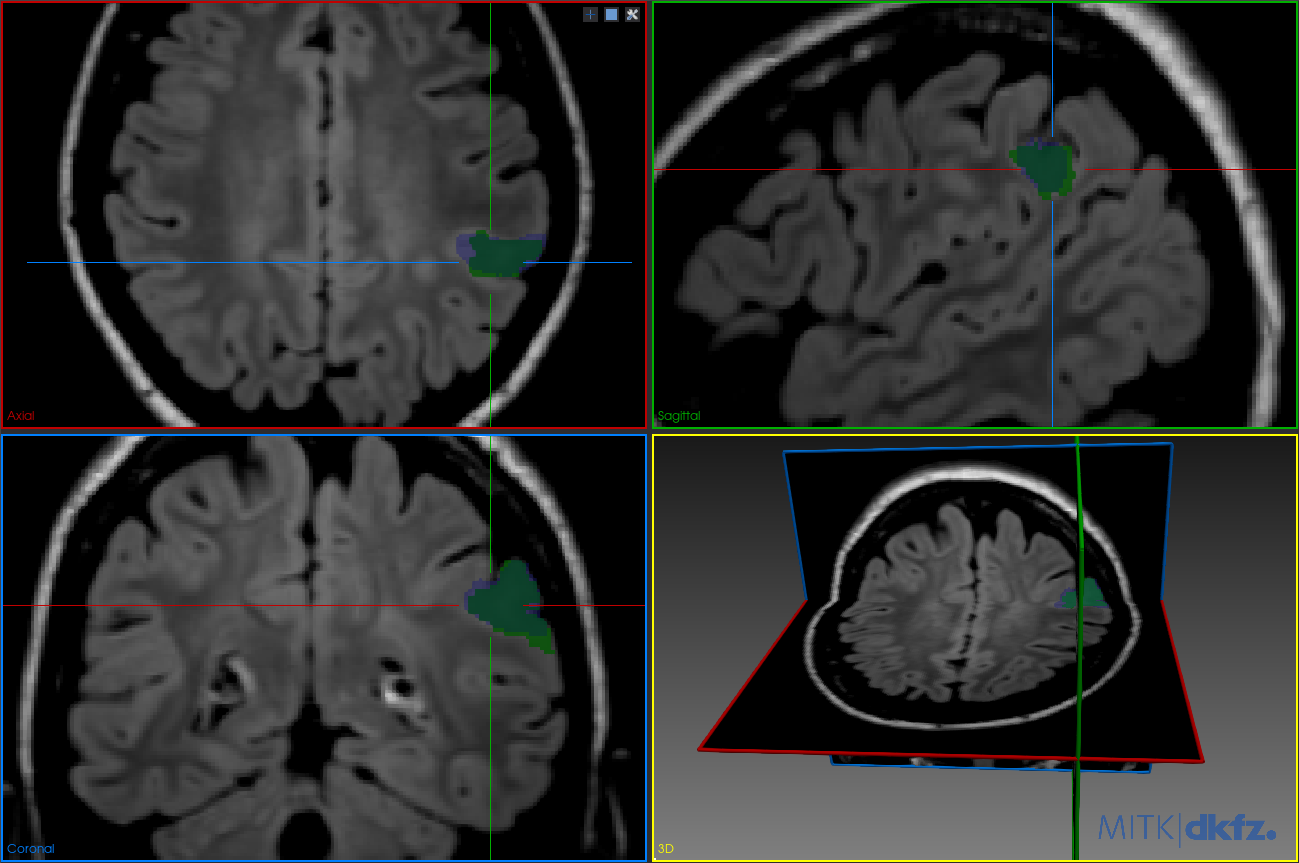

Figure 3 illustrates the segmentation results when the model is trained with the proposed TV loss added to Dice loss. In Figure 3(a), the predicted mask (blue) shows a high degree of overlap with the ground truth (green) and no visible false positives, even without post-processing. This highlights the regularizing effect of TV loss in enforcing spatial smoothness during training. In Figure 3(b), the result after post-processing (yellow mask) is nearly identical to the unprocessed prediction, confirming that TV loss had already smoothed the prediction to the extent that additional post-processing has minimal impact.

Refer to caption

(a) Model trained with TV loss. Green: ground truth mask; blue: predicted mask. The false positives are no longer present.

(b) Model trained with TV loss after post-processing. Green: ground truth mask; yellow: predicted mask. Minimal change, indicating TV loss already enforced spatial consistency.

Figure 3: Segmentation results with the proposed TV loss, before and after post-processing.